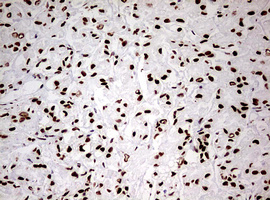

Immunohistochemical staining of paraffin-embedded Carcinoma of Human prostate tissue using anti-HNRNPM mouse monoclonal antibody. (Heat-induced epitope retrieval by 10mM citric buffer, pH6.0, 120°C for 3min, M06017-2)